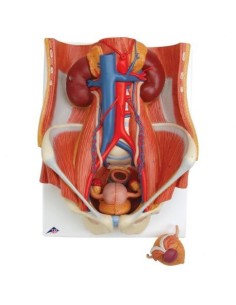

Scopri il Mondo dell’Anatomia con Modelli anatomici di Precisione

Benvenuto su Tuttoanatomia.it, il portale di riferimento in Italia per l’acquisto di modelli anatomici, poster, lettini portatili, simulatori medici e letteratura specialistica. Con i nostri modelli anatomici di 3B Scientific ed Erler Zimmer, leader mondiali nel settore, offriamo un’esperienza di apprendimento senza pari.

Modelli Anatomici Dettagliati per Ogni Necessità

Dal cranio in 22 parti con incastri magnetici ai modelli di colonna vertebrale, da quelli di articolazioni a quelli di cuore, ogni pezzo della nostra collezione è progettato per un’immersione totale nello studio dell’anatomia umana. I nostri modelli, realizzati tramite scansioni di ossa vere, garantiscono un’esperienza tattile autentica e una fedeltà di peso quasi identica agli originali.

Strumenti Didattici Innovativi per l’Educazione e la Pratica Medica

Essenziali per studenti e professionisti, i nostri modelli anatomici sono strumenti didattici che permettono di osservare le strutture anatomiche con precisione, eliminando la necessità di dissezioni o studi invasivi. Sono inoltre utili per spiegare ai pazienti le patologie, rendendo la comunicazione più efficace e risparmiando tempo prezioso.